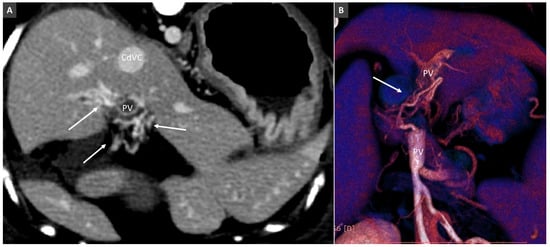

3.3. Portal Vein Aneurysm

- Bertolini, G.; Caldin, M. Computed tomography findings in portal vein aneurysm of dogs. Vet. J. 2012, 193, 475–480. [Google Scholar] [CrossRef] [PubMed]

- Miyawaki, S.; Washizu, M.; Maeda, S.; Shibata, S.; Watanabe, K.; Yamazoe, K. Portal vein aneurysm in a dog. J. Vet. Med. Sci. 2012, 74, 1191–1193. [Google Scholar] [CrossRef] [PubMed]